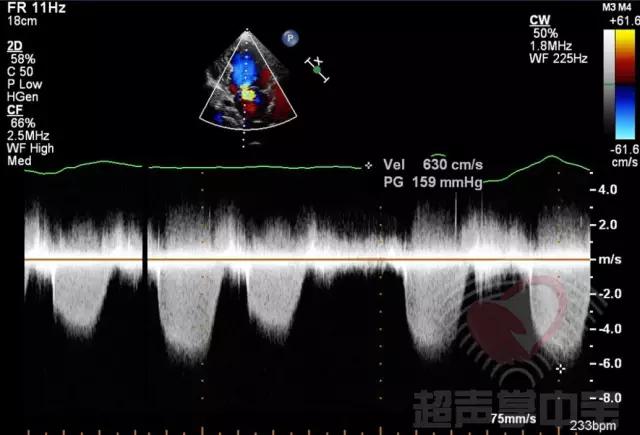

经典病例▏二尖瓣囊肿中竟然全是血液? 动态图7:CDFI:显示主动脉瓣中度反流,二尖瓣轻度反流,二尖瓣前叶附着的囊状物内收缩期充满花彩血流

经典病例▏二尖瓣囊肿中竟然全是血液? 图8:CW于囊状物内探及收缩期负向高速湍流,流速6.3m/s,压差159mmHg